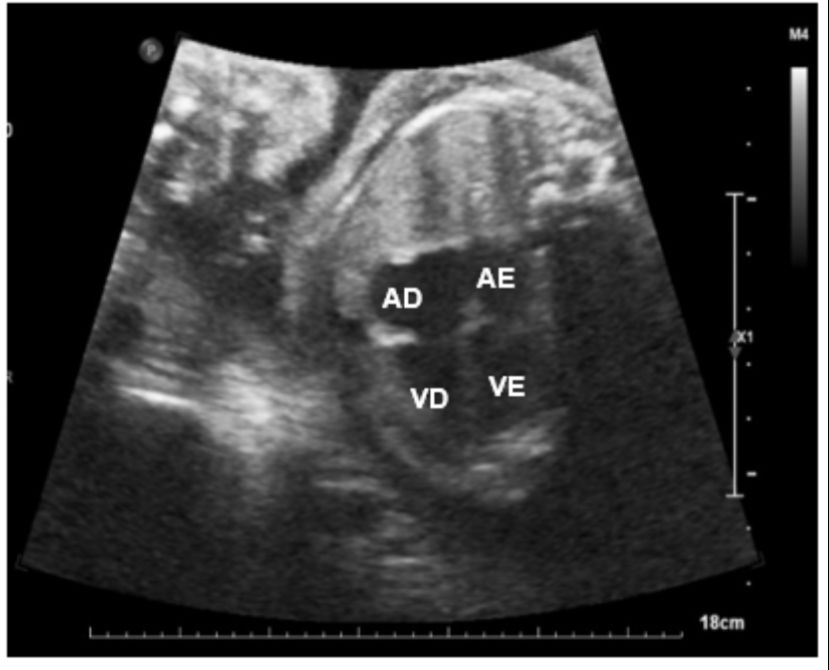

Ecocardiograma fetal mostrando a estrutura do coração (Imagem: Acervo do grupo de pesquisa)

O grupo de pesquisadores também publicou recentemente, no periódico EC Paediatrics (acesso via https://bit.ly/3IQNv3h), estudo de caso de gestante atendida no Hospital da UFSCar, com Covid-19 confirmada quando estava com 23 semanas e 6 dias de gravidez. O estudo relata que a mulher deixou de apresentar sintomas uma semana após o diagnóstico. Porém, 20 dias depois de ser diagnosticada, ultrassonografia em consulta de rotina identificou alterações no ritmo (taquicardia) e na estrutura do coração do feto. Foi, então, iniciado tratamento com o medicamento recomendado, bem como realizado acompanhamento semanal, com o bebê nascendo saudável na 38ª semana.

A partir do relato, os pesquisadores alertam para as possibilidades de alterações cardíacas nos fetos mesmo em caso de doença leve na mãe, que poderiam ter passado despercebidas frente à interrupção dos sintomas da Covid-19 na gestante. Assim, recomendam que mulheres grávidas diagnosticas com a doença sejam consideradas pacientes de alto risco e, assim, acompanhadas por profissionais qualificados, com avaliações frequentes, inclusive laboratoriais. Em relação aos exames a serem realizados, afirmam que, neste caso, a ecocardiografia fetal é essencial na aparição dos sintomas, na fase de convalescença e para controle quando alterações são identificadas.